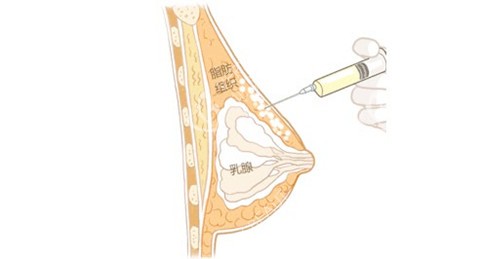

内窥镜双平面技术采用全程高清内窥镜操作,能够精密避开血管神经,将假体放置得既稳定又隐蔽,术后胸型自然度极高,连亲密家人都难以察觉手术痕迹。

麻醉生效后,首先在预定位置(通常为乳晕缘或乳房下皱襞)做长约4-5cm的切口,然后在内窥镜引导下精细剥离胸大肌后间隙或双平面空间,这一步骤对术后假体的稳定性和手感至关重要。

整个手术过程出血量少,魏院长轻柔精密的操作比较大程度地减少了组织损伤,为术后快速修复奠定了基础。